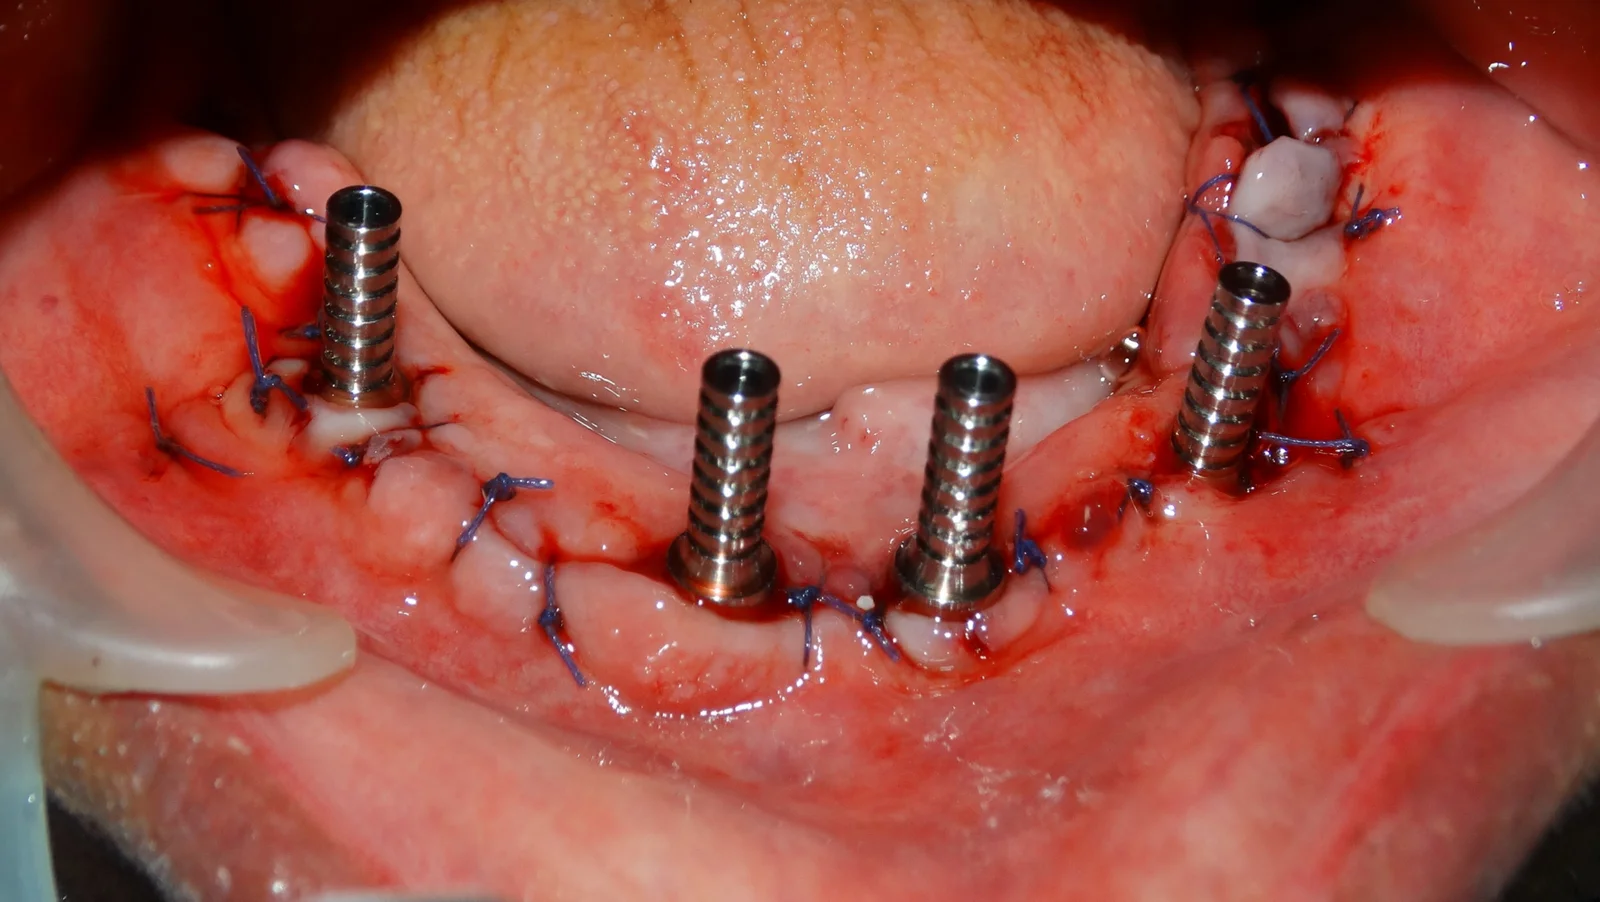

Clinical Case Progression

Full Mouth Rehabilitation

Implant Supported Fixed Teeth

Replacing all missing teeth with a permanent, fixed prosthesis that mimics the look, feel, and function of natural teeth. Explore our clinical transformations below.

All on Four Implants

What is All on Four?

All On Four is a new concept in implantology, where we can replace all the teeth with fixed prosthesis with the help of FOUR implants in each jaw.